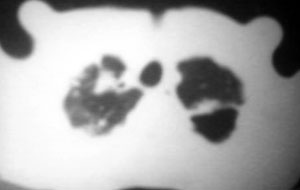

以下是引用逸风在2006-9-12 14:57:00的发言:[br]ct显示双肺上叶点片状及纤维索条状密度不均影,肺野外带近胸膜可见大小不等的含气空腔,壁略厚,境界清晰,未见液平面,中下肺野散在小片状及点状高密度影;纵隔内显示点状钙化,未见明显淋巴结肿大,构成胸廓诸骨未见明显异常.[br]诊断意见:1.双肺结核合并支气管播散;2.双肺上肺大泡.